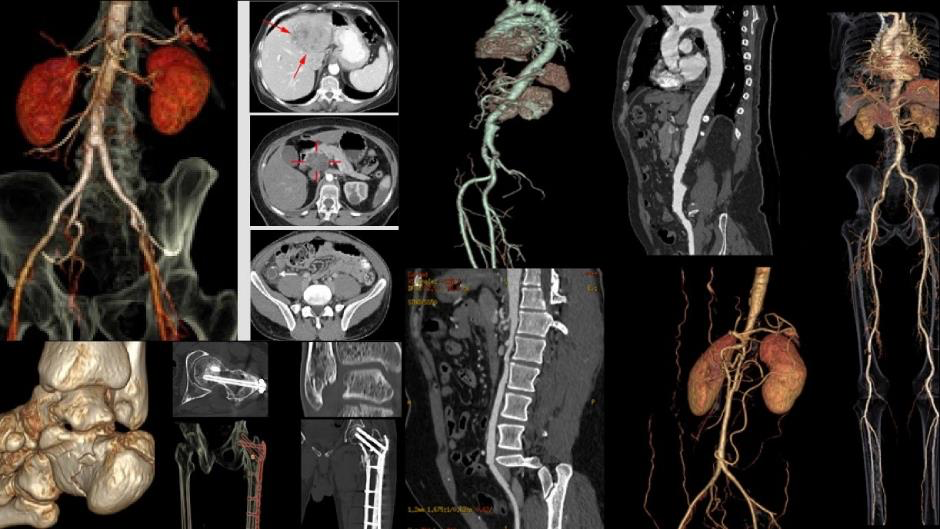

Hình ảnh học CT Scan tái hiện rõ nét các chi tiết bên trong cơ thể, giúp bác sĩ phát hiện sớm những tổn thương và nguy cơ bệnh lý tiềm ẩn

Bernard Healthcare và các bác sĩ Bernard hiện là thành viên của Hiệp hội Ningen Dock Nhật Bản. Dựa trên hướng dẫn tiêu chuẩn quốc tế, đội ngũ bác sĩ cùng Hội đồng Y khoa Bernard đã xây dựng và nâng cấp gói tầm soát chuyên sâu Ningen Dock Bernard, với đầy đủ trang thiết bị hiện đại như MRI thế hệ mới tích hợp AI, CT Scan, nội soi hiện đại…, đáp ứng tiêu chuẩn của các gói chuyên sâu nhất theo hướng dẫn của Hiệp hội.